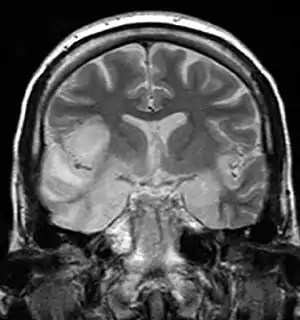

| MRI scan image shows high signal in the temporal lobes and right inferior frontal gyrus in someone with HSV encephalitis. | |

Limbic encephalitis refers to inflammatory disease confined to the limbic system of the brain. The clinical presentation often includes disorientation, disinhibition, memory loss, seizures, and behavioral anomalies. MRI imaging reveals T2 hyperintensity in the structures of the medial temporal lobes, and in some cases, other limbic structures. Some cases of limbic encephalitis are of autoimmune origin.[16]

- Brain scan, done by MRI, can determine inflammation and differentiate from other possible causes.